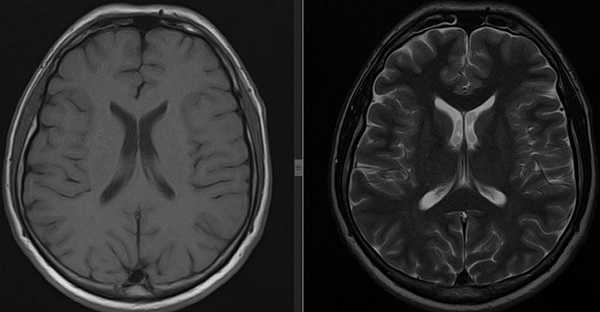

МРТ головного мозга. В аксиальной плоскости отмечается повышение интенсивности МР-сигнала в области ячеек сосцевидного отростка левой височной кости (круг) вследствие ранее перенесенных воспалительных изменений.

МРТ головного мозга. На мрт в аксиальной плоскости отмечается объемное образование внутреннего слухового прохода слева (стрелка), с четкими и неровными контурами, деформирующее окружающие структуры. После внутривенного введения парамагнитного контрастного вещества отмечается интенсивное и неоднородное его накопление образованием (изображение справа) — невринома.